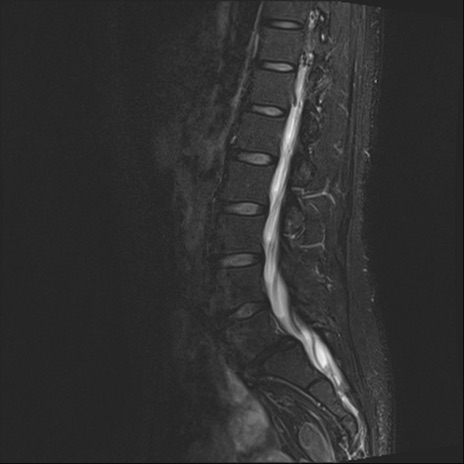

腰椎MRI

横断像と矢状断像